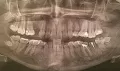

Восьмой зуб вверху вырос в щеку и на нем сейчас есть дырка, наверное, из-за кариеса. Можно вылечить или удалять?

Также на 6 внизу на снимке показано, что есть воспаление (10 лет назад нервы удалены, каналы запломбированы), побаливает при жевании твердой пищи и ноет периодически. Также на некоторых других зубах есть кариес.

Восьмые зубы необходимо удалить все, можно оставить только 48, он стоит в зубном ряду и не создаёт скученность, и не страдает соседняя семерка. Во всех трёх остальных случаях Ваши зубы мудрости необходимо удалить как можно раньше.

На обеих нижних шестёрках имеется хронический воспалительный процесс обширных размеров, и если Вы незамедлительно не займётесь лечением, то вскоре мы получим капсулированную кисту, и как следствие, удаление.

Также много проблем, связанных с неправильным контактом между зубами.